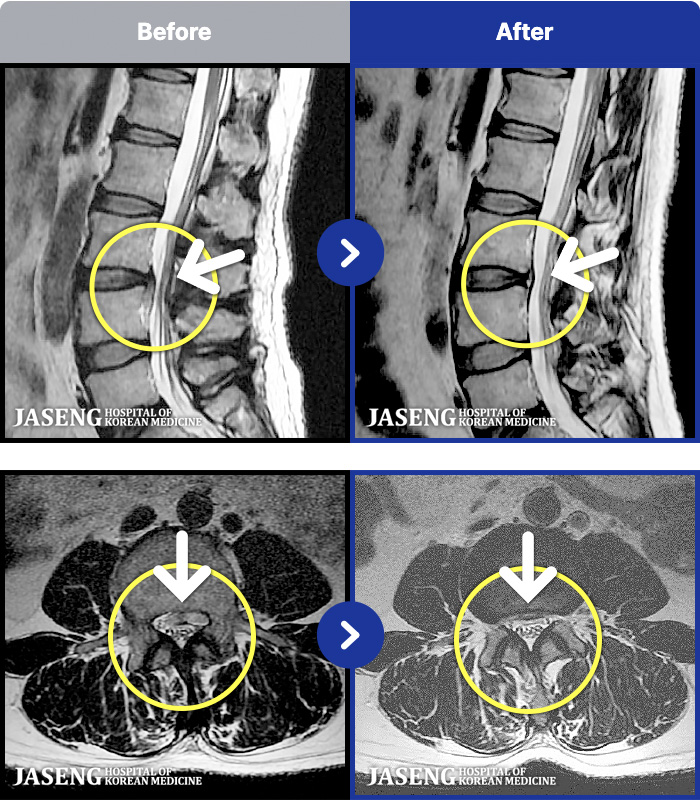

1,301 MRI ũ ʸ Ȯϼ.